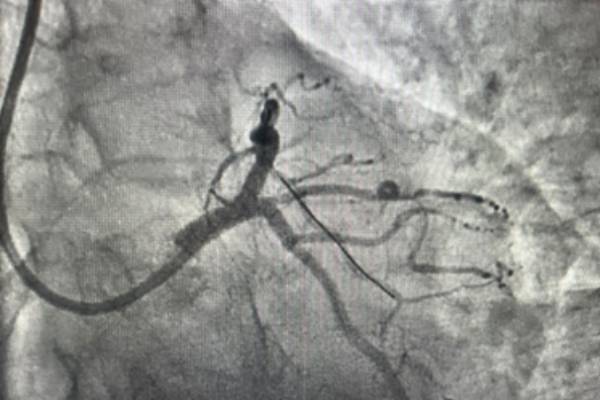

successful removal of Blockage through Angioplasty from the wrist (Rt Radial Artery) with one stent

4. Angiography Results: 90-95% blockage in one of the major blood vessels of the Heart (LAD)

5. Treatment: Removal of Blockage through Angioplasty from the wrist (Rt Radial Artery) with one stent

Before Treatment:

After Treatment:

4 days ago, A 60-year-old female was come to form complaining of regular chest pain. She said he experiencing regular chest pain for the last 1 week, but she ignore it’s a symptom of acidity the chest pain increased then he come to consult at Dr. Katik Bhosale’s Cardiology Clinic. First Our expert cardiologist Dr. Kartik Bhosale suggests some tests such as ECG, and Echo. As per the test results ECG was Abnormal but Echo was normal and the Chest pain was continuous. Then Dr. Kartik Bhosale Decides the Angiography which showed 90-95% blockage in one of the major blood vessels of the Heart (LAD). So it was not her Acidity problem but it was blockages in her heart vessel causing her chest pain. So subsequently Dr. Kartik Bhosale did Angioplasty from the wrist (Rt Radial Artery) and removed Blockage with one stent. There was no restriction of movement and was asked to walk immediately after Angioplasty. She was discharged the next day. Now patient is comfortable and chest pain free.